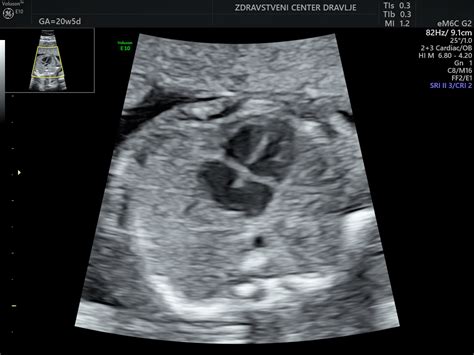

Kako je videti vaš otrok? V 23. tednu nosečnosti je otroček velik kot grenivka! Povprečni plod v 23. tednu meri skoraj 30 cm, če merimo od vrha glave do stopala in tehta okrog pol kilograma. Ja, otroček je že kar velik in končno ga je mogoče tehtati v kilogramih! Trenutno si v šestem mesecu nosečnosti. Vaš otrok zdaj hitro pridobiva težo. V tej fazi je otrokova koža še vedno prosojna in se zdi, kot da mu je malce prevelika. To je zato, ker raste hitreje kot njegovo telo, ki jo nato s kopičenjem maščob in rastjo dohiti. Zdaj bi že morali občutiti redno gibanje svojega otroka. Otrokove okončine so zdaj v pravem sorazmerju, vaše malo bitjece pa postaja vedno bolj podobno ljubkemu dojenčku, ki ga pričakujete. V naslednjih nekaj tednih boste čutili premike teh daljših okončin, saj je otrok še naprej zelo aktiven.

Ko obiskujete svojega ginekologa samo enkrat mesečno, se v tem tednu z njim ne morete posvetovati in izvesti ultrazvoka. Uživajte v prostem času! V tretjem trimesečju boste ginekologa morda obiskovali bolj pogosto, vsak drugi teden.